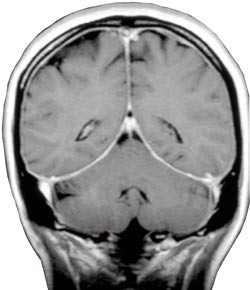

Pasient 1. Tidligere frisk 41 år gammel kvinne som fikk akutte smerter i nakke, hode og interskapulært mens hun syklet. Etter hvert fikk hun blikkfokuseringsvansker og diplopi. Ved innleggelse, 14 dager etter symptomdebut, hadde hun høyresidig abducensparese. Nevrologisk status var ellers normal. På direkte spørsmål angav hun smertefrihet om natten. MR med angiografi av intracerebrale kar viste ikke patologiske forhold, men det ble bemerket økt signal svarende til dura på de protonvektede bildene. Ved spinalpunksjon var det nødvendig å aspirere for å få ut væske. Diagnosen spontan intrakranial hypotensjon ble stilt på bakgrunn av klinisk bilde og null i spinalvæsketrykk. Cerebral MR med gadoliniumkontrast bekreftet diagnosen (fig 1). Det var også typiske funn ved MR av medulla, men det var ikke mulig å finne noe sikkert lekkasjepunkt (fig 2).

Typisk funn ved cerebral MR er diffus meningeal fortykkelse med gadoliniumkontrastopptak (5) – (9). Man tror dette skyldes dural vasodilatasjon og større konsentrasjon av kontrastmateriale i dural mikrovaskulatur og i interstitiell væske. Basis for denne antakelsen er den såkalte Monroe-Kellie-doktrinen, som sier at redusert spinalvæskevolum fører til kompensatorisk vasodilatasjon i hjerne og meninger (5, 8). Andre typiske MR-funn er tegn til nedfall av hjernen, forstørret hypofyse pga. hyperemi, subdural væskeansamling og forstørrede venesinuser (5, 8, 9). Spinal MR kan vise epidural væskeansamling med signal som spinalvæske, spinale hygromer, dilatasjon av cervikale epidurale vener og sammenfalt duralsekk (10) – (12).